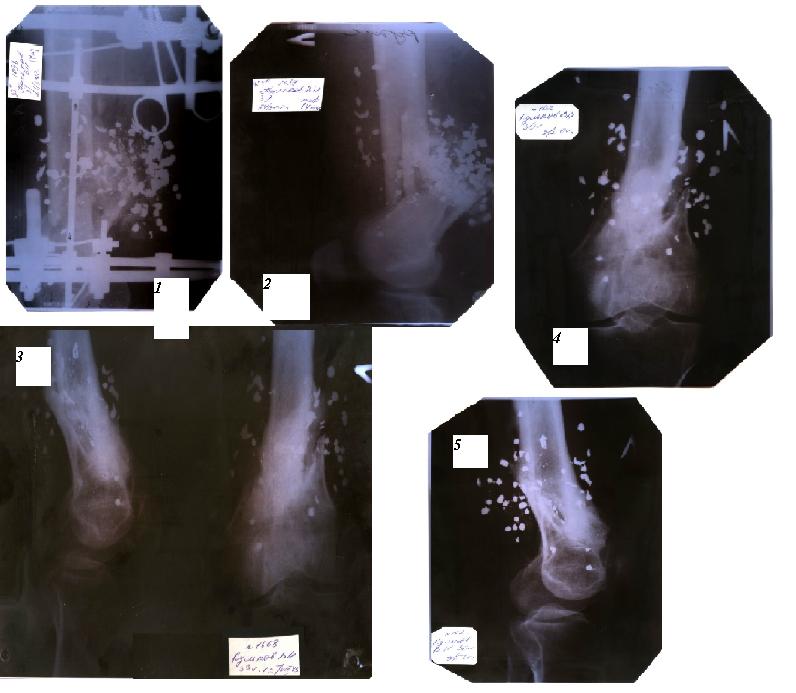

Травма произошла 24.03.02 - прострелили дробью №3 с очень близкого расстояния 2-3 м.

Вся дробь (примерно 80-90 шт) вместе с пыжами и частью ватных штанов была в ноге. Произошел перелом( на снимке хорошо видно) и сам мыщелок тоже развалился на 2 фрагмента (на отсканированных снимках вино плохо). 10 мес ходил с одним аппаратом Иллизарова, потом сделали повторную репозицию и 4 мес с другим. Сняли в конце мая прошлого года. На данный момент сустав активно работает около 70 град, пассивно градусов до 100-110(с очень большим усилием). Укорочение конечности 4 см. Коллеги! Подскажите что лучше сделать в данном случае? Разработать сустав, а потом удлинять конечность? либо наоборот? У больного уже есть признаки начального деф. артроза тазобедренного сустава (боли при ходьбе и небольших нагрузках).